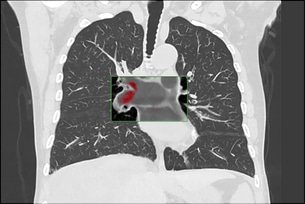

Post Graduate Institute of Medical Education and Research (PGIMER) “This is an exceptional IMR case as NCCT KUB was done at a radiation dose exposure (0.6 mSv) equivalent to Xray KUB and yet produced images with exquisite details. A tiny 3 mm calculus was seen in right kidney on IMR images which was not seen on other imaging modalities (USG, KUB) as well as on images produced by standard reconstruction. Hence low dose CT with IMR benefited this case to a great extent.”

India

Dr. Khandelwal & Team